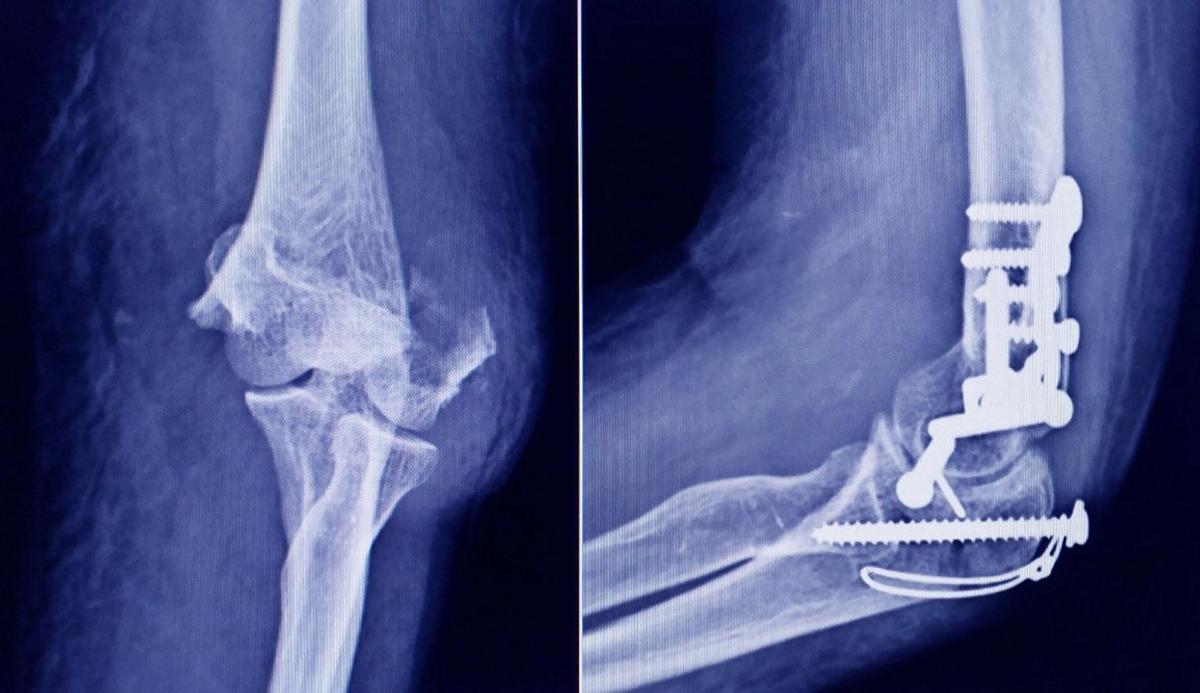

Buenos Aires, 8 enero (NA) – La Administración Nacional de Medicamentos, Alimentos y Tecnología Médica (ANMAT) advirtió a la población por un tornillo utilizado en cirugías traumatológicas debido a que es falso, por lo que su uso representa riesgo para la salud del paciente al que se lo implante.

Se trata de un tornillo utilizado en cirugías traumatológicas que fue detectado durante una inspección de control de mercado realizada en una ortopedia ubicada en la ciudad de San Miguel de Tucumán.

Dicho tornillo es producido por la firma Stryker Corporation, que se encuentra registrada ante ANMAT bajo el PM 594-139. Luego de la inspección, se exhibió la muestra recolectada ante la responsable técnica de dicha empresa, quien afirmó que se trataba de un producto falsificado.

Las autoridades de la ANMAT dieron a conocer las características del producto para su advertencia: STRYKER 10 mm X 28 mm - BIOABSORBABLE - ACL INTERFERENCE SCREW - REF 234-010-067 - LOT 90905.